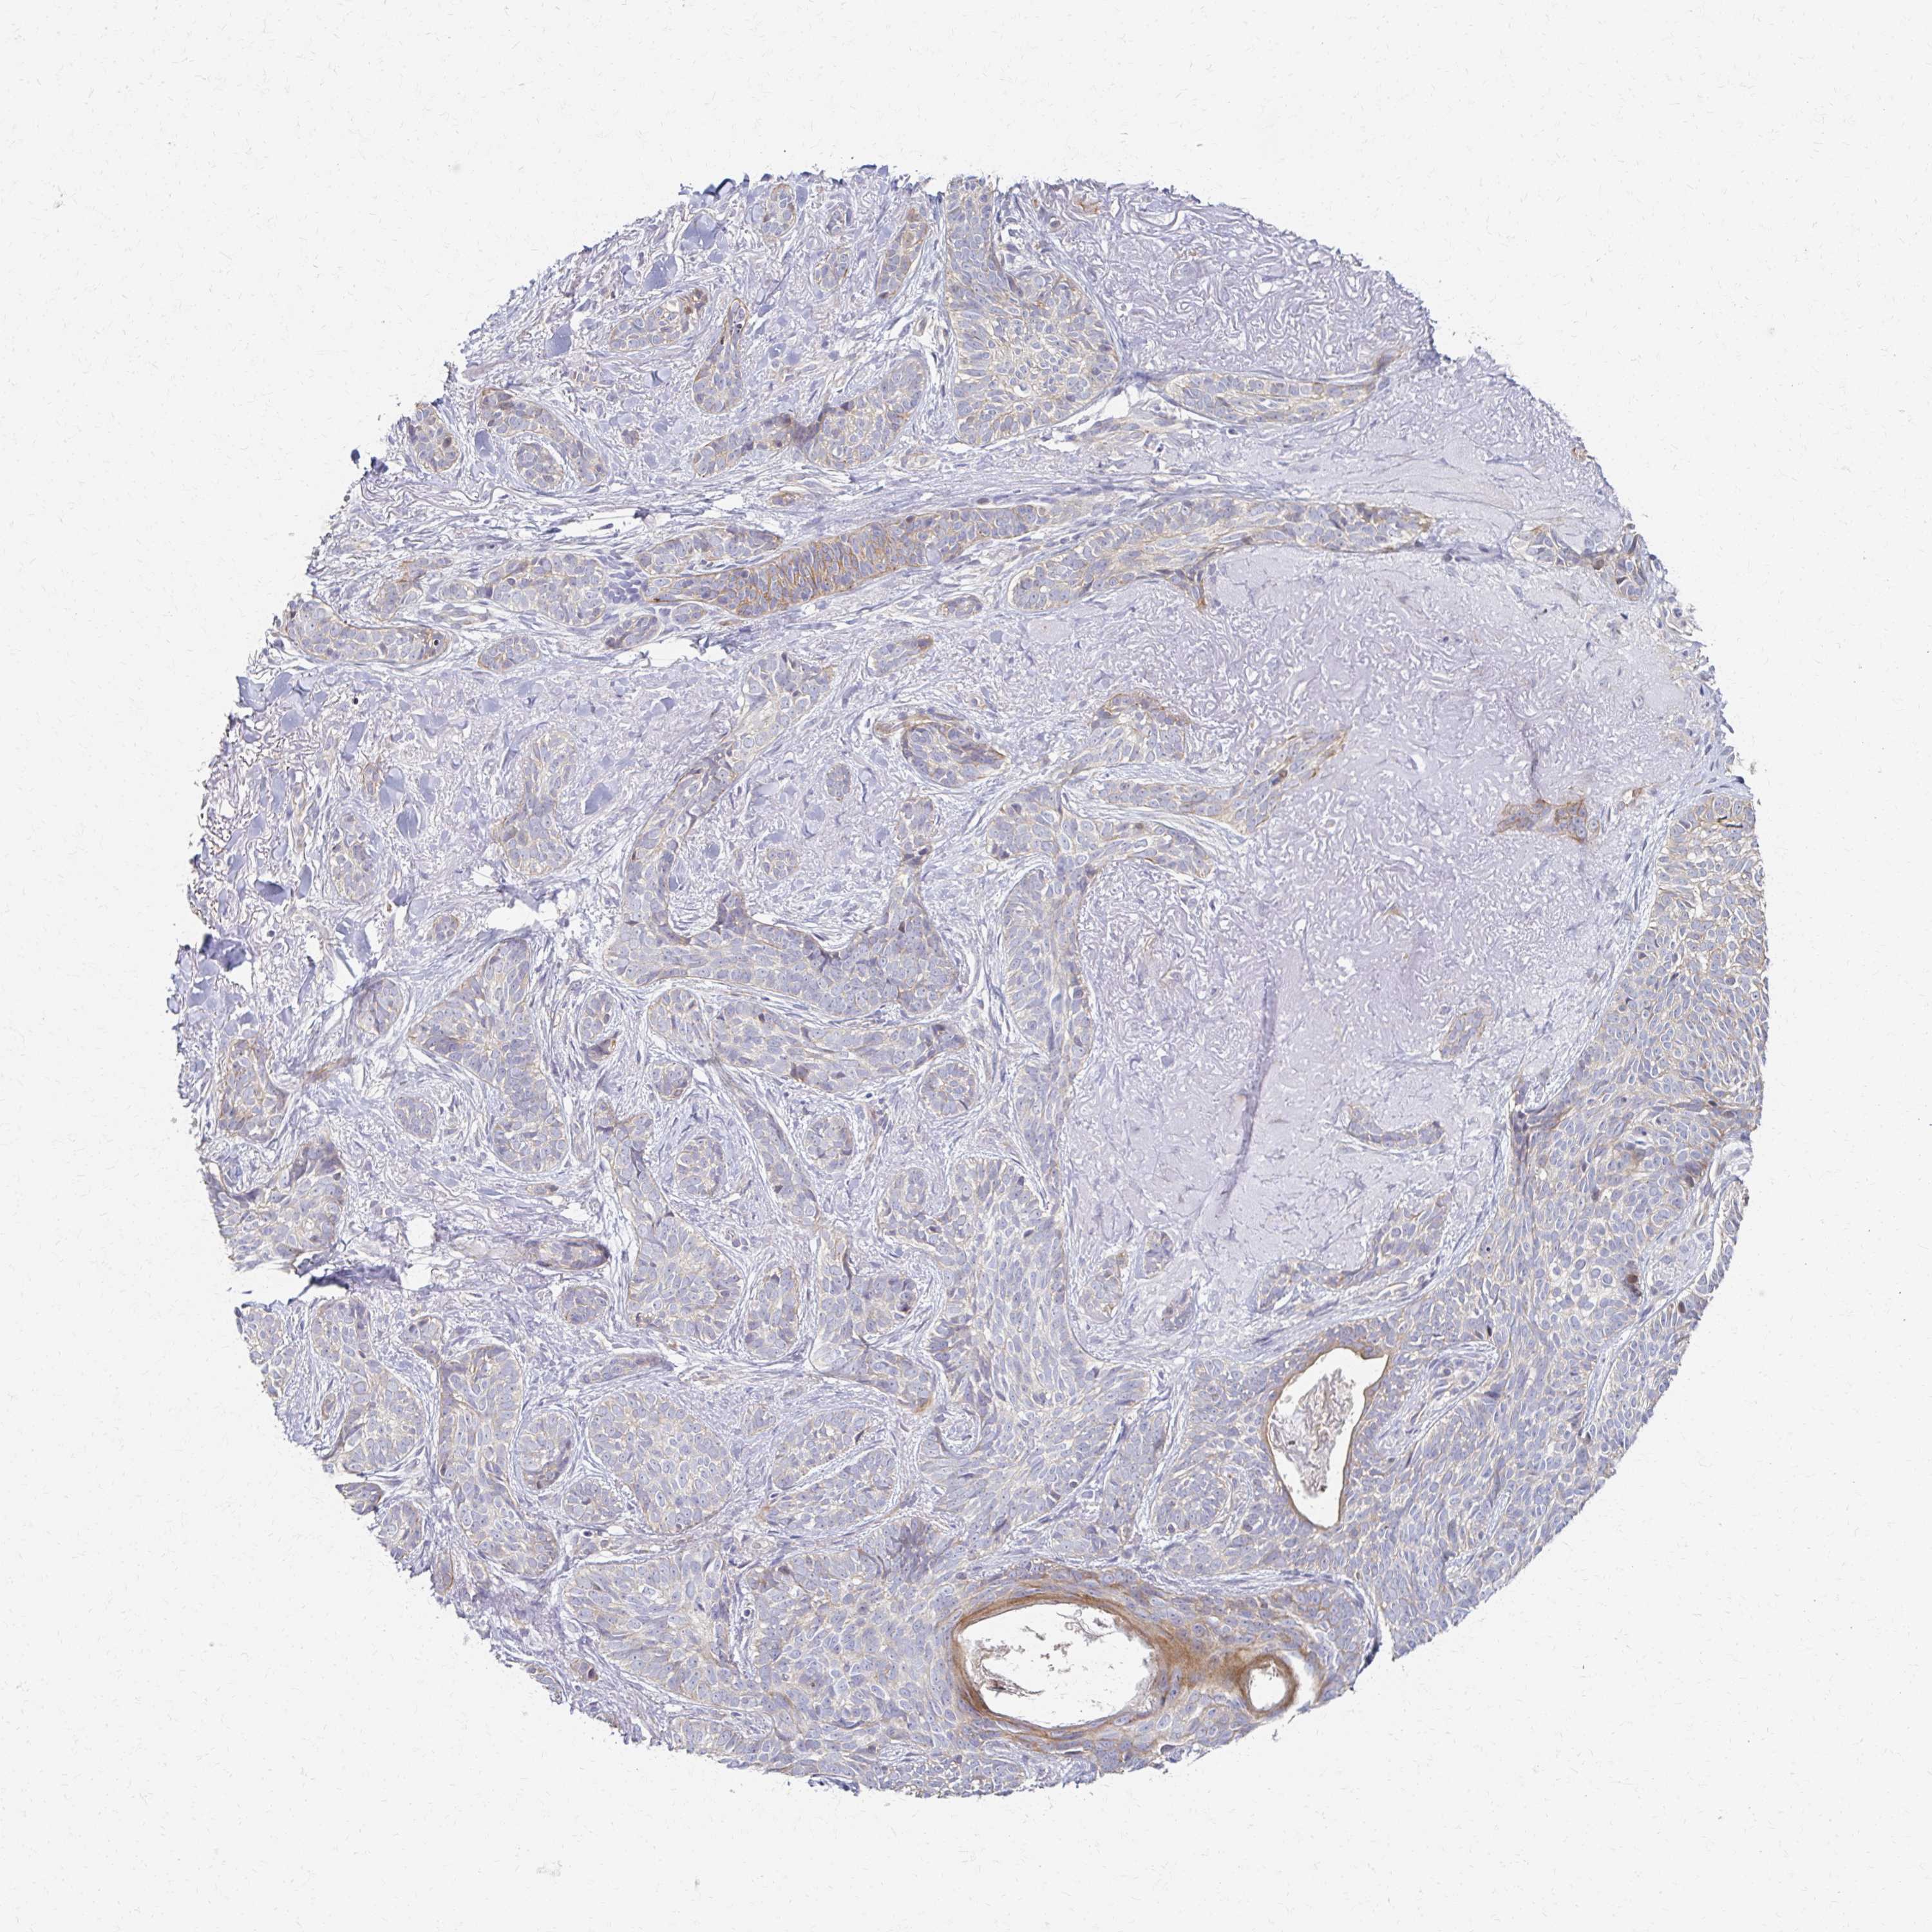

SKIN CANCER - Protein expressioni

A mouse-over function shows sample information and annotation data. Click on an image to view it in a full screen mode. Samples can be filtered based on level of antibody staining by selecting one or several of the following categories: high, medium, low and not detected. The assay and annotation is described here.

Each image is clickable and will lead to virtual microscopy that enables deeper exploration of all samples and also displays staining intensity scores, fraction scores and subcellular localization as well as patient and tissue information for each sample.

Antibody HPA059235

Staining

High

Medium

Low

Not detected

Intensity

Strong

Moderate

Weak

Negative

Quantity

>75%

75%-25%

<25%

None

Location

Nuclear

Cytoplasmic/membranous

Cytoplasmic/membranous,nuclear

Squamous cell carcinoma, NOS